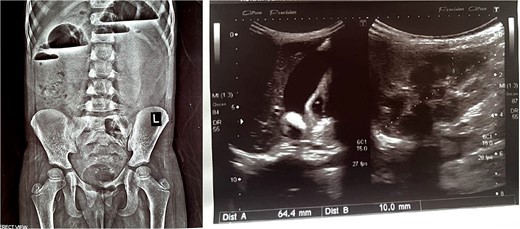

The patient experienced an uneventful postoperative course during her hospital stay and was discharged home with scheduled outpatient psychiatric follow-up. However, she presented again after 3 weeks with severe abdominal pain, tenderness, and recurrent vomiting. Imaging studies, including abdominal X-rays and ultrasounds, revealed the presence of air-fluid levels (Fig. 4, left) and confirmed intussusception (Fig. 4, right). Attempts to resolve the intussusception through non-surgical means, such as enema reduction, were unsuccessful. Consequently, a repeat upper midline laparotomy was performed, revealing jejunojejunal intussusception, which was successfully managed through manual reduction. The recurrent intussusception was determined to be attributable to postoperative adhesions.

X-ray abdomen erect showing air fluid levels (left). Ultrasound abdomen showing intussusception (right).